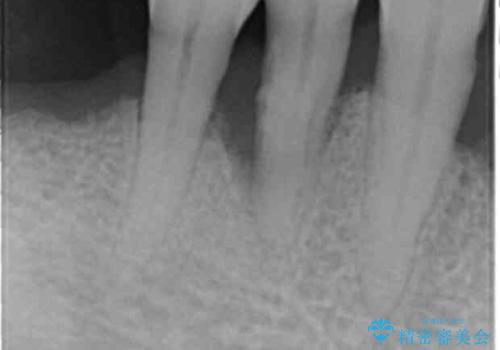

精査したところ、全顎的な重度の歯周病により下顎前歯に激しい動揺を認めました。

再生療法から1年後リエントリー手術により骨の再生を確認し、骨外科処置(骨を平らにして歯周ポケットの根本的な改善を図る処置)を行ったのち、連結補綴を行いました。

骨吸収と動揺が著しい前歯1本(左下1)のみ抜歯しております。

再生療法と骨外科処置により、歯周ポケットは全周2mm以下に改善されました。